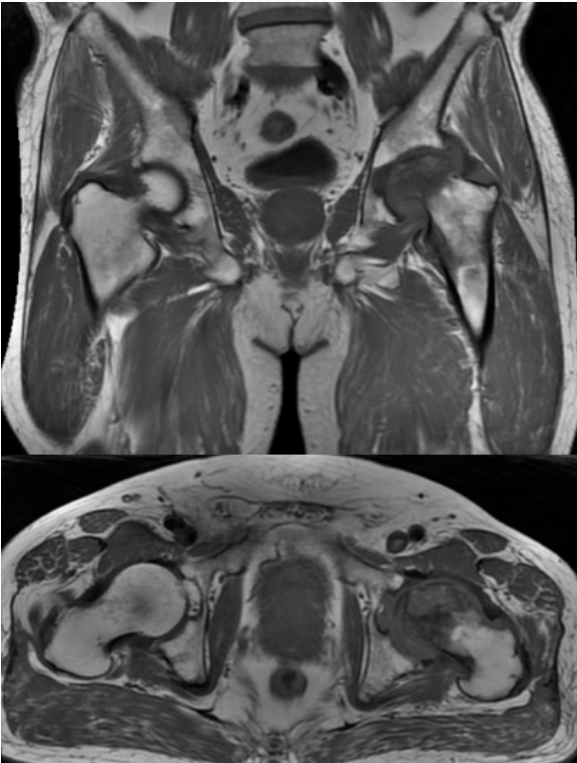

MRI结果显示,王先生的左侧股骨头已经变扁,出现局部塌陷。

左侧股骨头变扁,局部塌陷,骨质内见线状T1WI低信号,髋臼及股骨近端骨松质见片状T1WI低、T2WI压脂高信号,DWI高信号,周围滑膜增厚,邻近软组织肿胀,PD压脂信号增高,关节腔少量积液。

在这个病例中,磁共振(MRI)发挥了无可替代的作用。与X光片只能显示骨骼形态、CT主要显示骨质结构不同,MRI的突出优势在于:

多序列、多参数成像:如同本例中运用的T1WI、T2WI压脂、DWI、PD压脂等不同序列,能从血流、水分、细胞密度等多个维度评估病变性质,为医生提供全面的诊断信息。